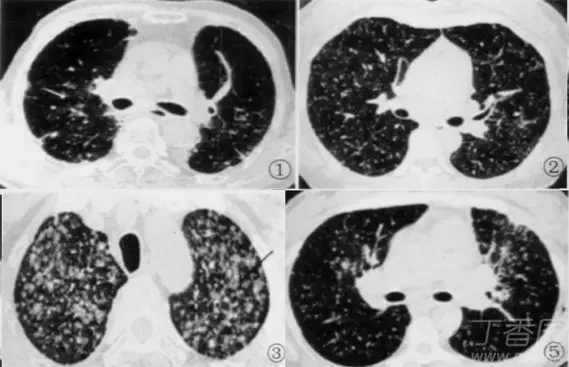

粟粒性肺结核丨ct表现诊断要点

肺粟粒样结节鉴别诊断

图 2 左肺尖肺癌并肺内转移 下肺静脉层面 hrct 显示两肺大量粟粒